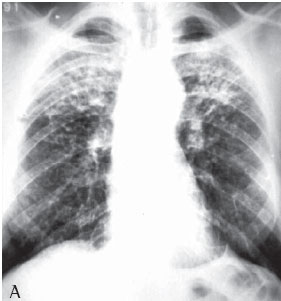

RESULTS

All 75 patients with accelerated silicosis were male. The mean age was 43 years (range, 28-76 years). The mean duration of exposure was 14.2 years (range, 7 months-38 years). Of the 75 patients, 62 (82.6%) were sandblasters, 11 (14.6%) were blacksmiths, 1 (1.4%) was a welder, and 1 (1.4%) was a metal polisher. In reference to concomitant tuberculosis, 39 patients reported a history of pulmonary tuberculosis (52%). Of those, 37 developed the disease during their exposure to silica.The diagnosis was confirmed in 31 cases: 24 through direct sputum smear microscopy; 3 through direct mycobacteria culture of the sputum; 1 through mycobacteria culture of the bronchoalveolar lavage fluid; and 3 through histopathology. In 8 patients, there was clinical and radiological suspicion of tuberculosis based on a response to specific treatment. The radiological classification of the large opacities seen on the chest X-rays was as follows: Type A in 23 patients (30.7%); Type B in 25 (33.3%); and Type C in 27 (36%) (Figures 1A and 1B). Of the cases analyzed, 74 presented bilateral conglomerate masses, whereas only 1 presented unilateral lesion (Figures 2A and 2B).

On a simple chest X-ray, accelerated silicosis is characterized by large opacities (over 1 cm in diameter), with nonsegmentally distributed, homogenous areas of consolidation, principally affecting the upper fields.

The lesions tend to form on the periphery, migrating toward the hilum, creating a zone of emphysematous lung tissue between the consolidation and the pleural surface. The borders of the large opacities are irregular and poorly defined. As the disease progresses, the masses tend to shrink. Emphysematous lesions and bullae then appear surrounding the masses and at the lung bases. The lungs gradually lose volume. The large masses seen in accelerated silicosis are capable of causing cavitation due to the resultant ischemia and necrosis. Nevertheless, cavitation is a relatively uncommon finding in silicosis. When it does occur, one should first consider tuberculosis. The pleural thickening frequently observed in tuberculosis is also commonplace in PMF, although pleural effusion is extremely rare.(17)

The greater the profusion of nodules on the chest X-ray (categories 2 and 3), the greater are the odds of evolving to PMFThe chest X-ray generally shows large lung opacities against a background of diffuse pulmonary nodule formation. However, PMF has been reported in the absence of pulmonary nodule formation, since the silicosis nodules present reduced visibility due to their incorporation within the fibrous mass.(18)

The chest X-rays of more than half of the accelerated silicosis patients showed large type B or C opacities, denoting the seriousness of the disease in these patients.